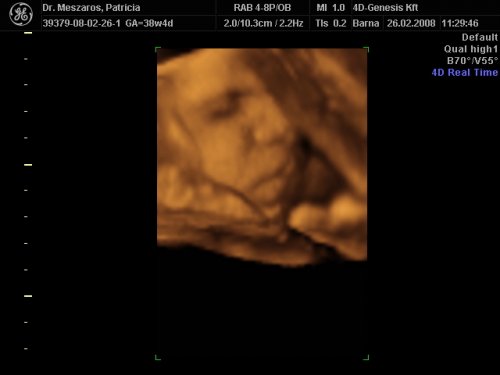

A doki szerint pufók kislány